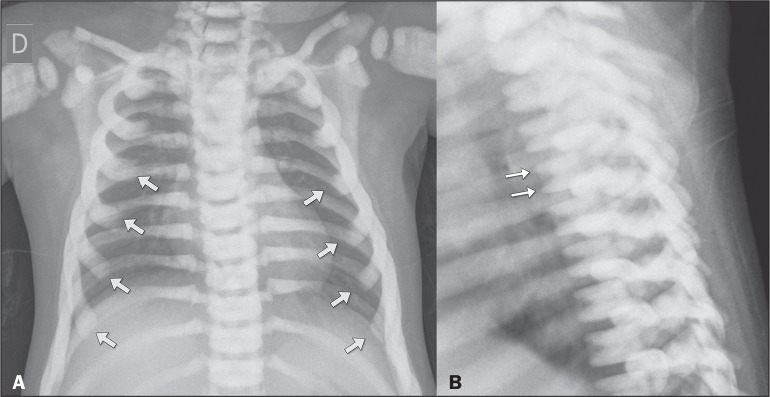

硬化性骨发育不良包括骨密度异常,分为遗传性和非遗传性形式。主要通过x线摄影诊断,通常是偶然发现的。在遗传形式中,以下是最突出的:骨质疏松症、骨质疏松症、多发性骨干硬化(肋病)、纹状骨病和Camurati-Engelmann病。在非遗传性形式中,髓内骨硬化和骨质疏松症具有特定的影像学特征。主要的鉴别诊断包括成骨细胞转移、结节性硬化症和肾性骨营养不良,由于它们的相似性,需要仔细鉴别。

Sclerosing bone dysplasias encompass abnormalities in bone density, divided into hereditary and nonhereditary forms. Primarily diagnosed through radiography, they are often incidental findings. Among the hereditary forms, the following stand out: osteopetrosis, osteopoikilosis, multiple diaphyseal sclerosis (ribbing disease), osteopathia striata, and Camurati-Engelmann disease. Among the nonhereditary forms, intramedullary osteosclerosis and melorheostosis present specific radiographic characteristics. The main differential diagnoses include osteoblastic metastases, tuberous sclerosis, and renal osteodystrophy, requiring careful differentiation because of their similarities.